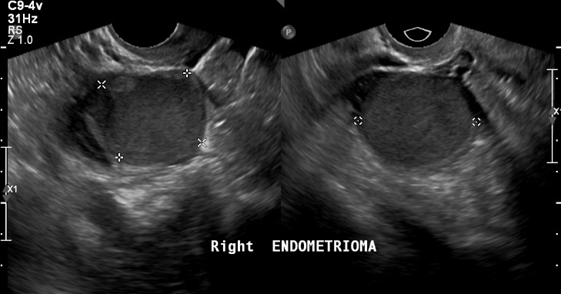

In patients without endometriosis, the average longitudinal measurement of the uterus was 7.5cm with a range of 5cm to 8.5cm and the average transverse measurement was 5.0cm with a range of 4.5cm-6.4cm (Figure 1).26 In the presence of endometriosis, this size increased depending on the size and site of the endometrioma. The Figure 2 shows dilation of the uterine cavity due to the presence of endometrioma. In this patient, the transverse measurement increased to 6.5cm (Figures 3a & 3b).

Figure 1 An ultrasound image of the uterus showing normal size. The horizontal line shows longitudinal measurement (7.5 cm), and the vertical line shows transverse measurement (5 cm).

Figure 3a An ultrasound image of the uterus showing left endometrioma. The dots indicate size of masses present.

Figure 3b An ultrasound image of the uterus showing right endometrioma. The dots indicate size of masses present.